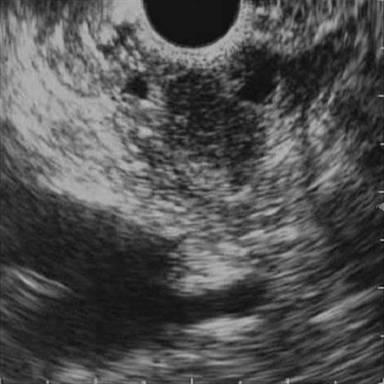

A 63-year-old male had two episodes of acute pancreatitis by biochemistry and abdominal ultrasonography. EUS findings showed an ampullary mass and cystic dilatation of terminal portion of duct of Wirsung suggestive of wirsungocele (Figures 1 and 2). EUS guided FNA from the ampulla suggested a neuroendocrine tumor. MRCP confirmed EUS findings of wirsungocele and ampullary mass (Figure 3). ERCP (Figure 4) and endoscopic ampullectomy was then performed and patient made an uneventful recovery. The histopathological examination and immunohistochemistry showed neuroendocrine tumor (pathological classification: G1) with cells expressing synaptophysin and chromogranin (Figure 5). The Mib proliferation index was less than 2%. The pancreatic duct was seen well dilated within the tumor tissue.

Figure 2. EUS of the ampullary region showing hypoechoic lesion at the ampulla. The wirsungocele is also seen. |